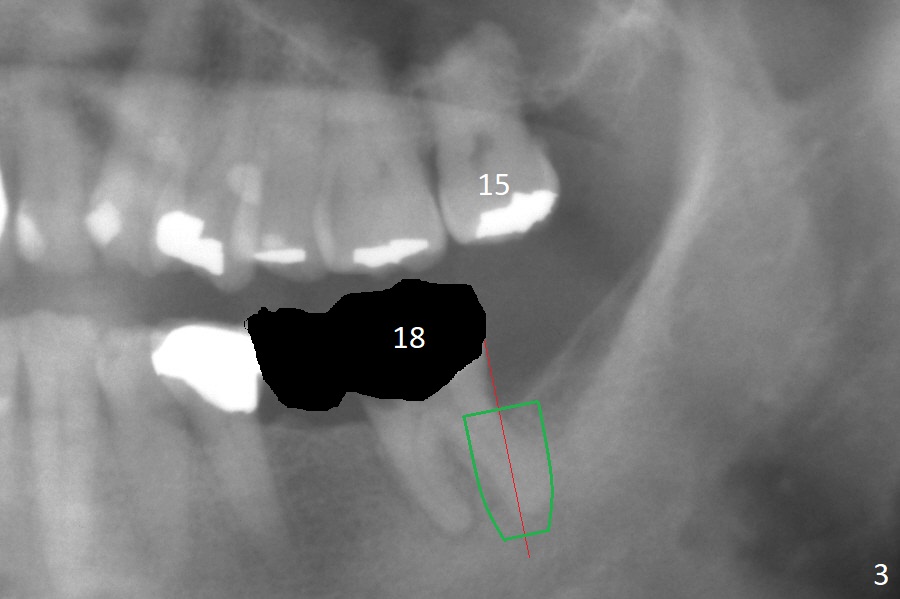

After extraction of the residual root at #18 (Fig.1), the septum is narrow, while the distal socket seems to be the most appropriate site for implant placement (Fig.2 (M: mesial)).  In fact the implant needs to tilt slightly distally (relative to the original trajectory of the distal socket, Fig.3 green) to occlude with the opposing tooth.  The implant at #19 could be placed more mesially (Fig.4 (*: Vera Graft)).

A drawback of placing an implant in the distal socket of the 2nd lower molar is closer to the Inferior Alveolar Canal.  The implants seem to have osteointegrated 4.5 months postop (Fig.5).  While the ridge at #19 appears to be wider than preop (as compared to Fig.1), that at #18 seems to be atrophic 5 months postop (Fig.6 * (1 week post cementation)).  The distal implant placement at #19 may increase possibility of abutment screw loosening during functioning (Fig.7 *).  When the patient returns for periodic exam 1.5 months post cementation, loose contact between the implant crowns is noted (Fig.8).  The bony trabeculae form between the 2 implants crestally 12 months postop, i.e., 7 months post cementation (Fig.9).  The loose contact between the 2 implants is corrected 14 months post cementation.